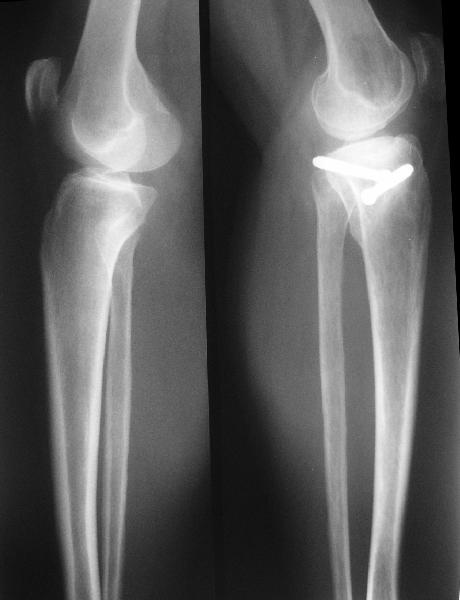

В отделение поступила пациентка из области, 68 лет. Травму получила год назад, находилась на лечении в ЦРБ по поводу перелома внутреннего мыщелка большеберцовой кости, была вот так прооперирована. На сегодняшний момент беспокоят боли в области коленного сустава при ходьбе, движения ограничены, от 180 до 100. При планировании операции возникли разногласия, на каком уровне делать остеотомию. То ли поднимать внутренний мыщелок, т.е. делать остеотомию через сустав, то ли обойтись внесуставной коррекцией оси. Второй вариант менее травматичен, но конгруэнтность сустава при этом останется нарушенной, улучшится только ось конечности. Допустима ли такая коррекция, или все-таки правильнее не менять взаимоотношения наружного мыщелка с диафизом, а поднять именно внутренний мыщелок?

По снимку видно, что и в наружном отделе сустава есть серьезные изменения.